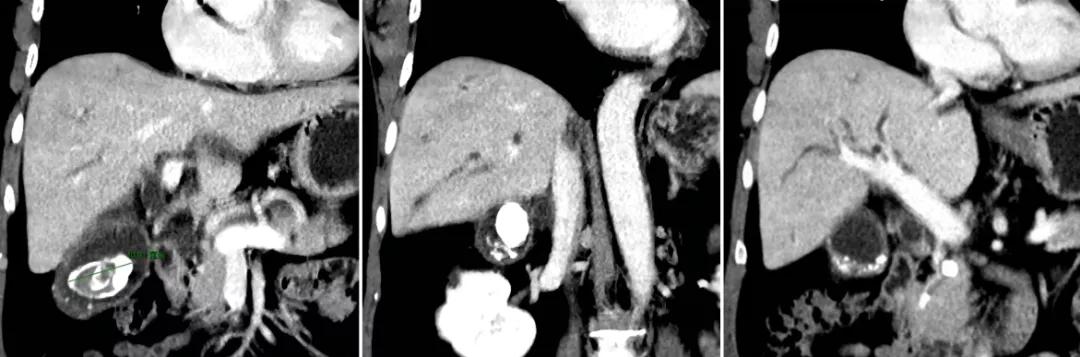

案例六

60岁女性,胆囊结石多年,一直未予重视,亦无规律随访复查。因偶然体检发现胆囊结石、胆囊占位就诊,完善检查后不排除胆囊癌,遂入院行“胆囊癌根治术(胆囊切除+肝部分切除+肝外胆管切除+区域淋巴结清扫+胆管-空肠吻合术)”,术后病例提示低分化胆囊腺癌,目前密切随访治疗中。